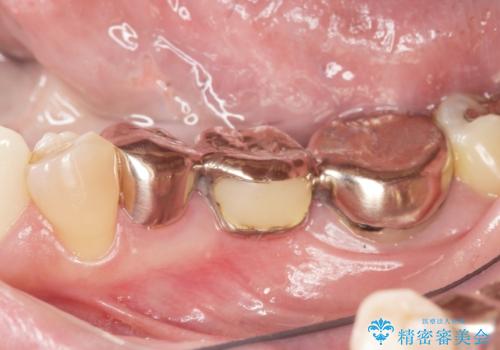

銀歯のブリッジをジルコニアブリッジへ

- 笑った時に大きく見えてしまう奥歯の銀歯ブリッジを白くしたいと希望され来院されました。

強度があり、審美性にも優れるジルコニアブリッジに置き替えていく治療計画としました。

- 39.6万円(ジルコニアクラウン×3・仮歯×3)費用は治療当時の料金となります